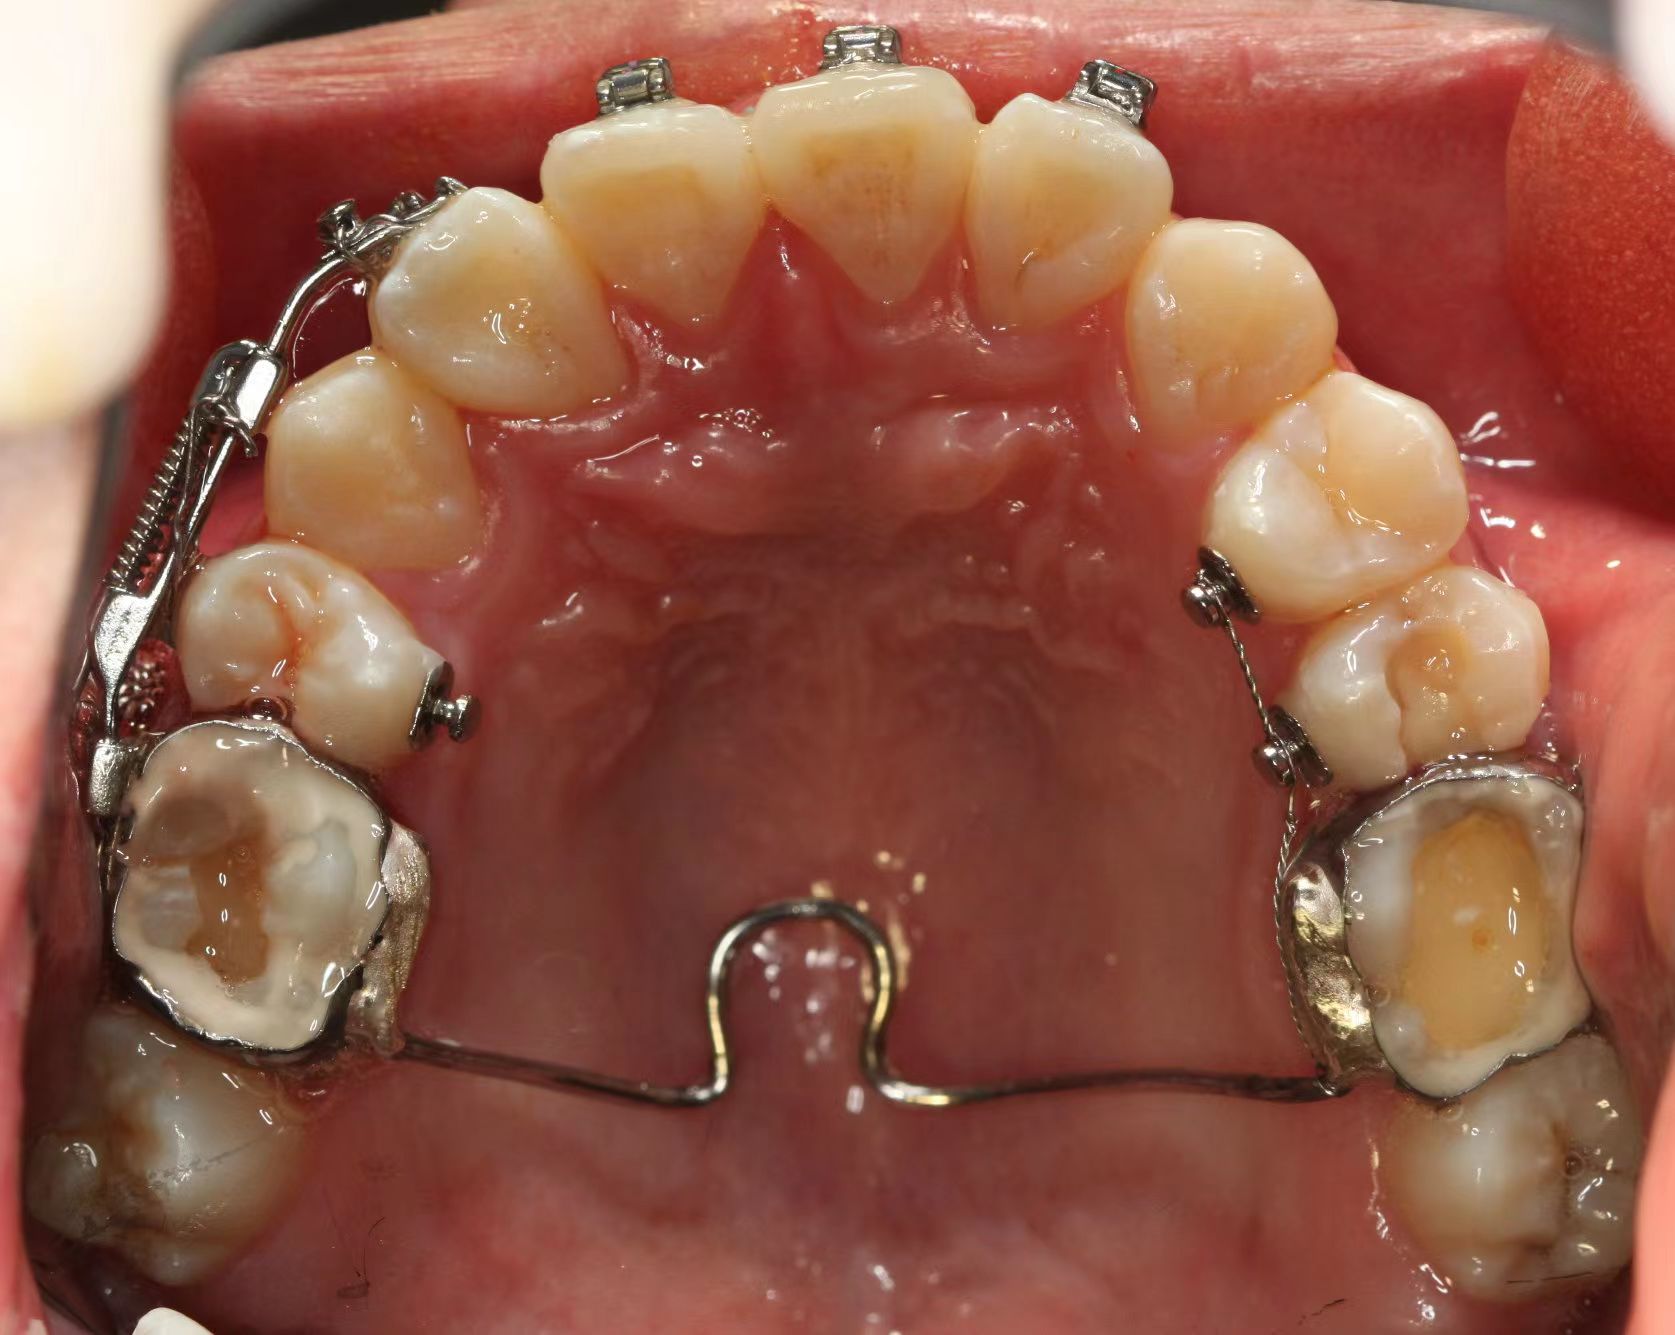

情况:不接受外科手术,在当地做了1年半的矫治,遇到困难无法进行。由外地正畸同行推荐来上海寻求非手术矫治的二手病例。武广增老师接收时的错合畸形情况,呈现严重的骨性反合偏合及侧方开合(图1-图10)。由于推荐其去口腔医院接受正颌外科手术遭到拒绝,武广增老师通过专业的检查、分析,制定一套详细的治疗计划,采用了磨牙推进器技术、武式辅弓技术等特色正畸手段获得明显效果(图2-1~图2-9)。治疗结束后也拍摄了相关照片(图3-1~图3-9)。

矫治效果

图2-1